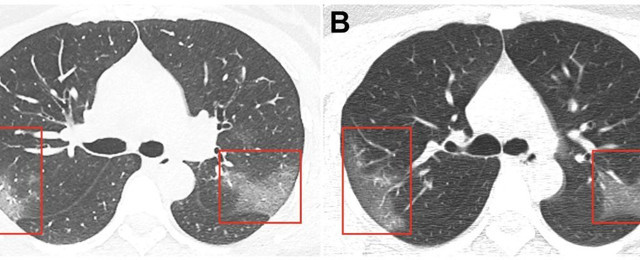

Bilgisayarlı tomografide akciğerlerde sıvı veya parçacık dolu keseler görüldü; bu durumun hastalık geliştikçe giderek kötüleşebileceği kaydedildi.

Hong Kong'un bulguları, Şubat 2020'nin başlarında Wuhan'ın önceden yapılan araştırmalarını doğruladı. Yakın tarihli bir çalışmada, Wuhan Üniversitesi Zhongnam Hastanesi'nden bilim insanları 140 koronavirüs hastasının akciğer taramasını analiz etti. Buna göre, her bir hastanın akciğerlerinde buzlu cam benzeri yapılar buldular.